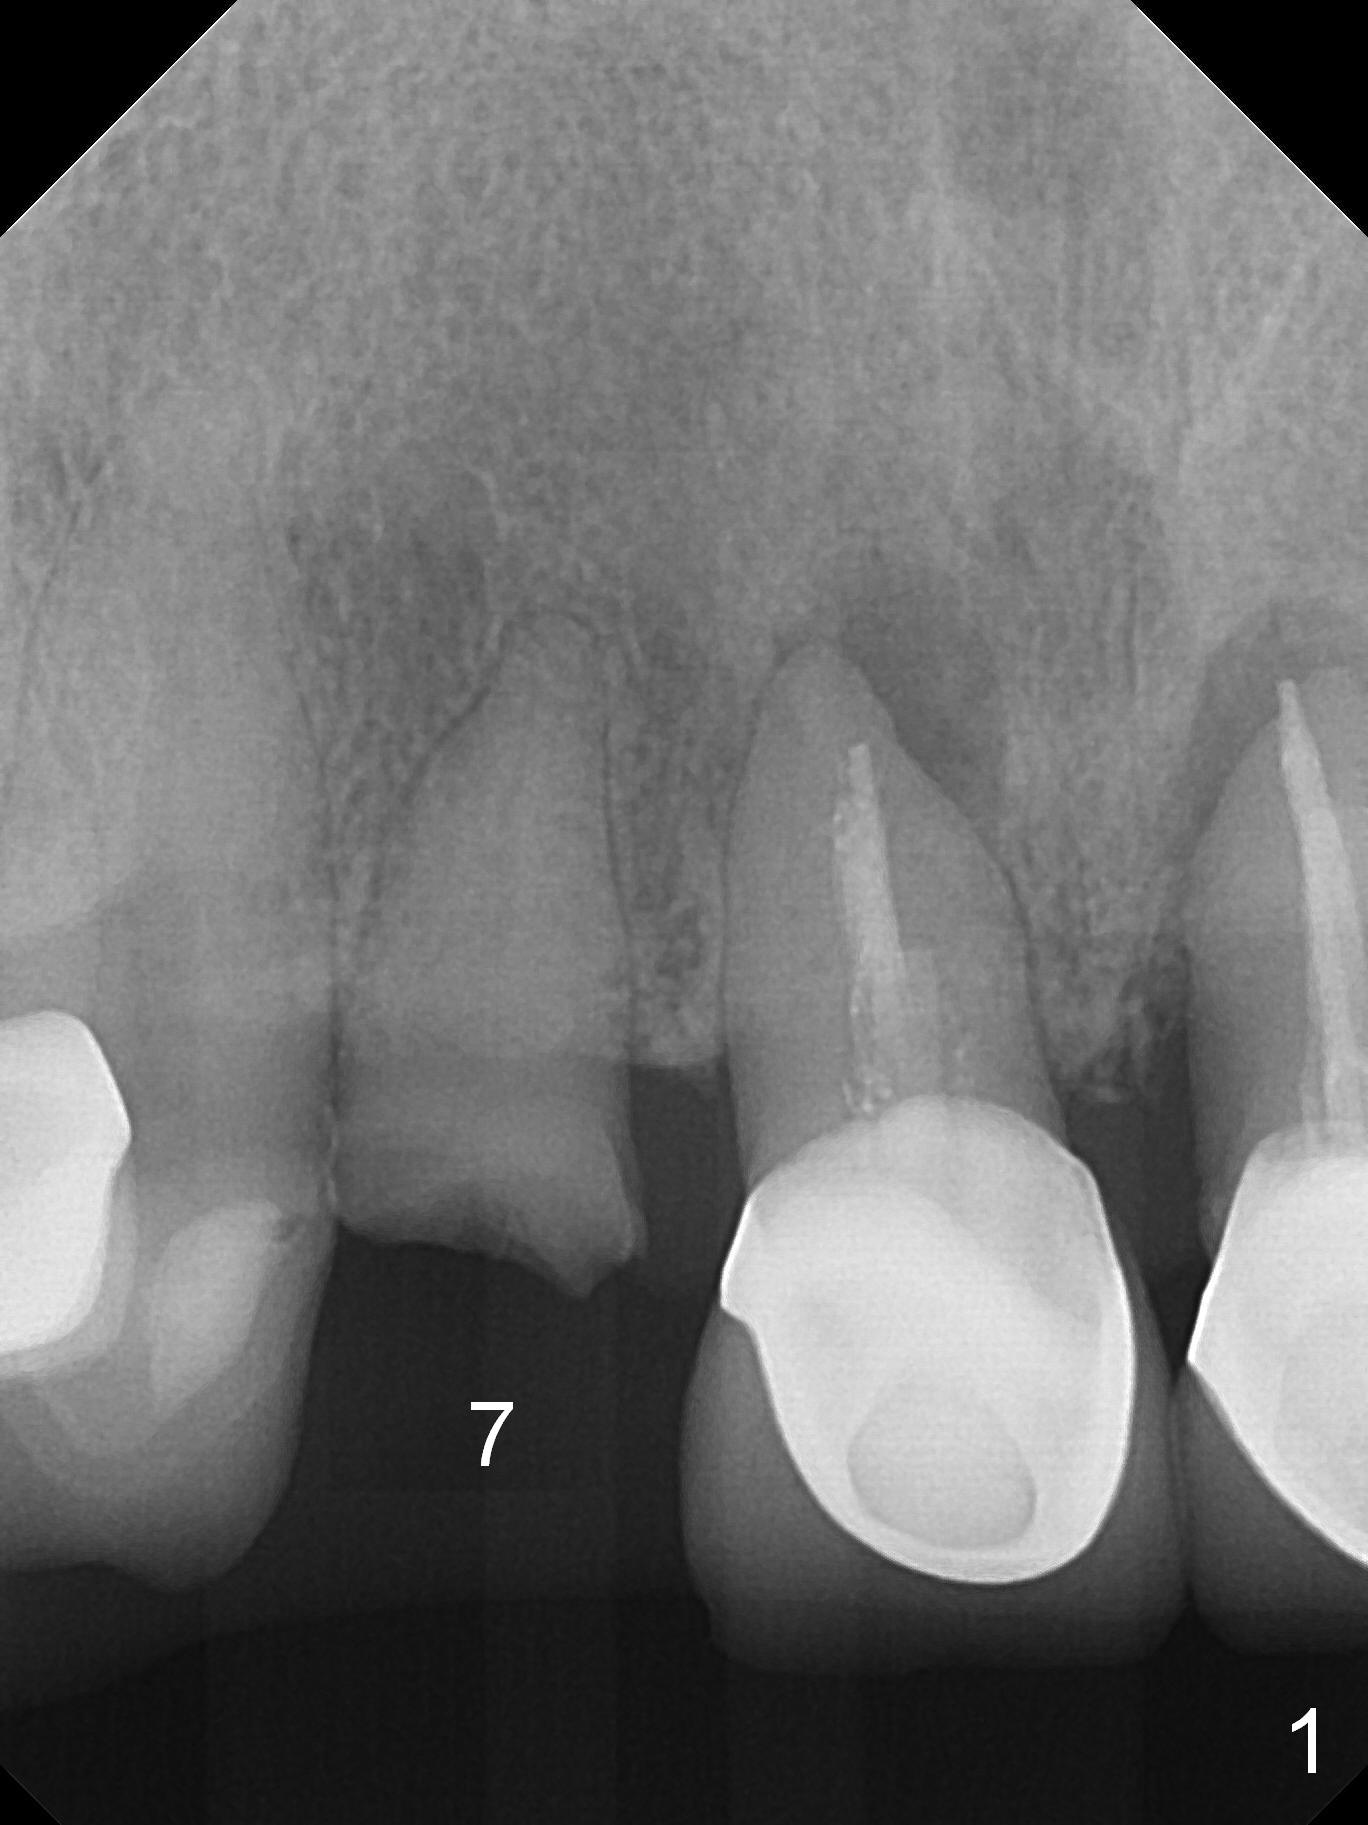

A 60-year-old woman has multiple restoration and no lower posterior teeth (replaced with RPD). The tooth #7 fractures (Fig.1). When an immediate implant is placed (Fig.2, no Antibiotic) with immediate provisional (using the existing crown), occlusal clearance is critical. Check overbite often and take photos. If the root seems to be ankylosed, socket shield will be performed.

She returns for impression 4 months postop; the abutment margin is substantially subgingival (Fig.6 arrow). The abutment is changed to 4.5x4(4) mm one before impression. There is no bone resorption 9 months post cementation (Fig.7).